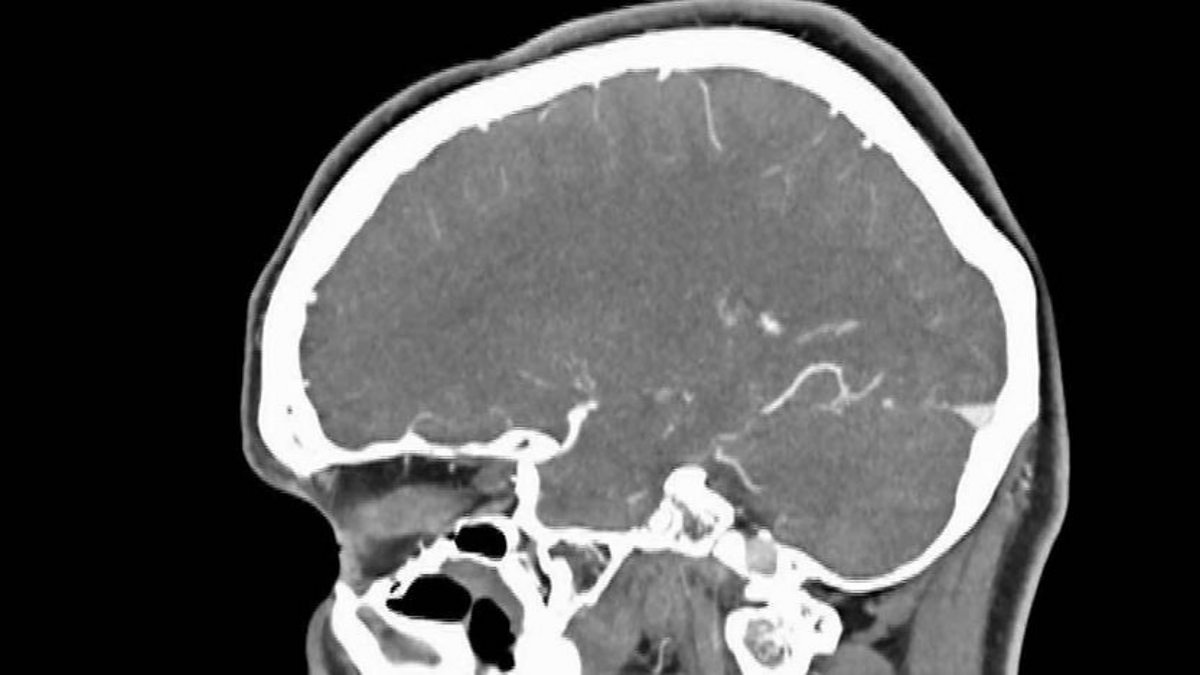

Richard Adams investigates the private health screening companies selling unnecessary tests to the worried well.